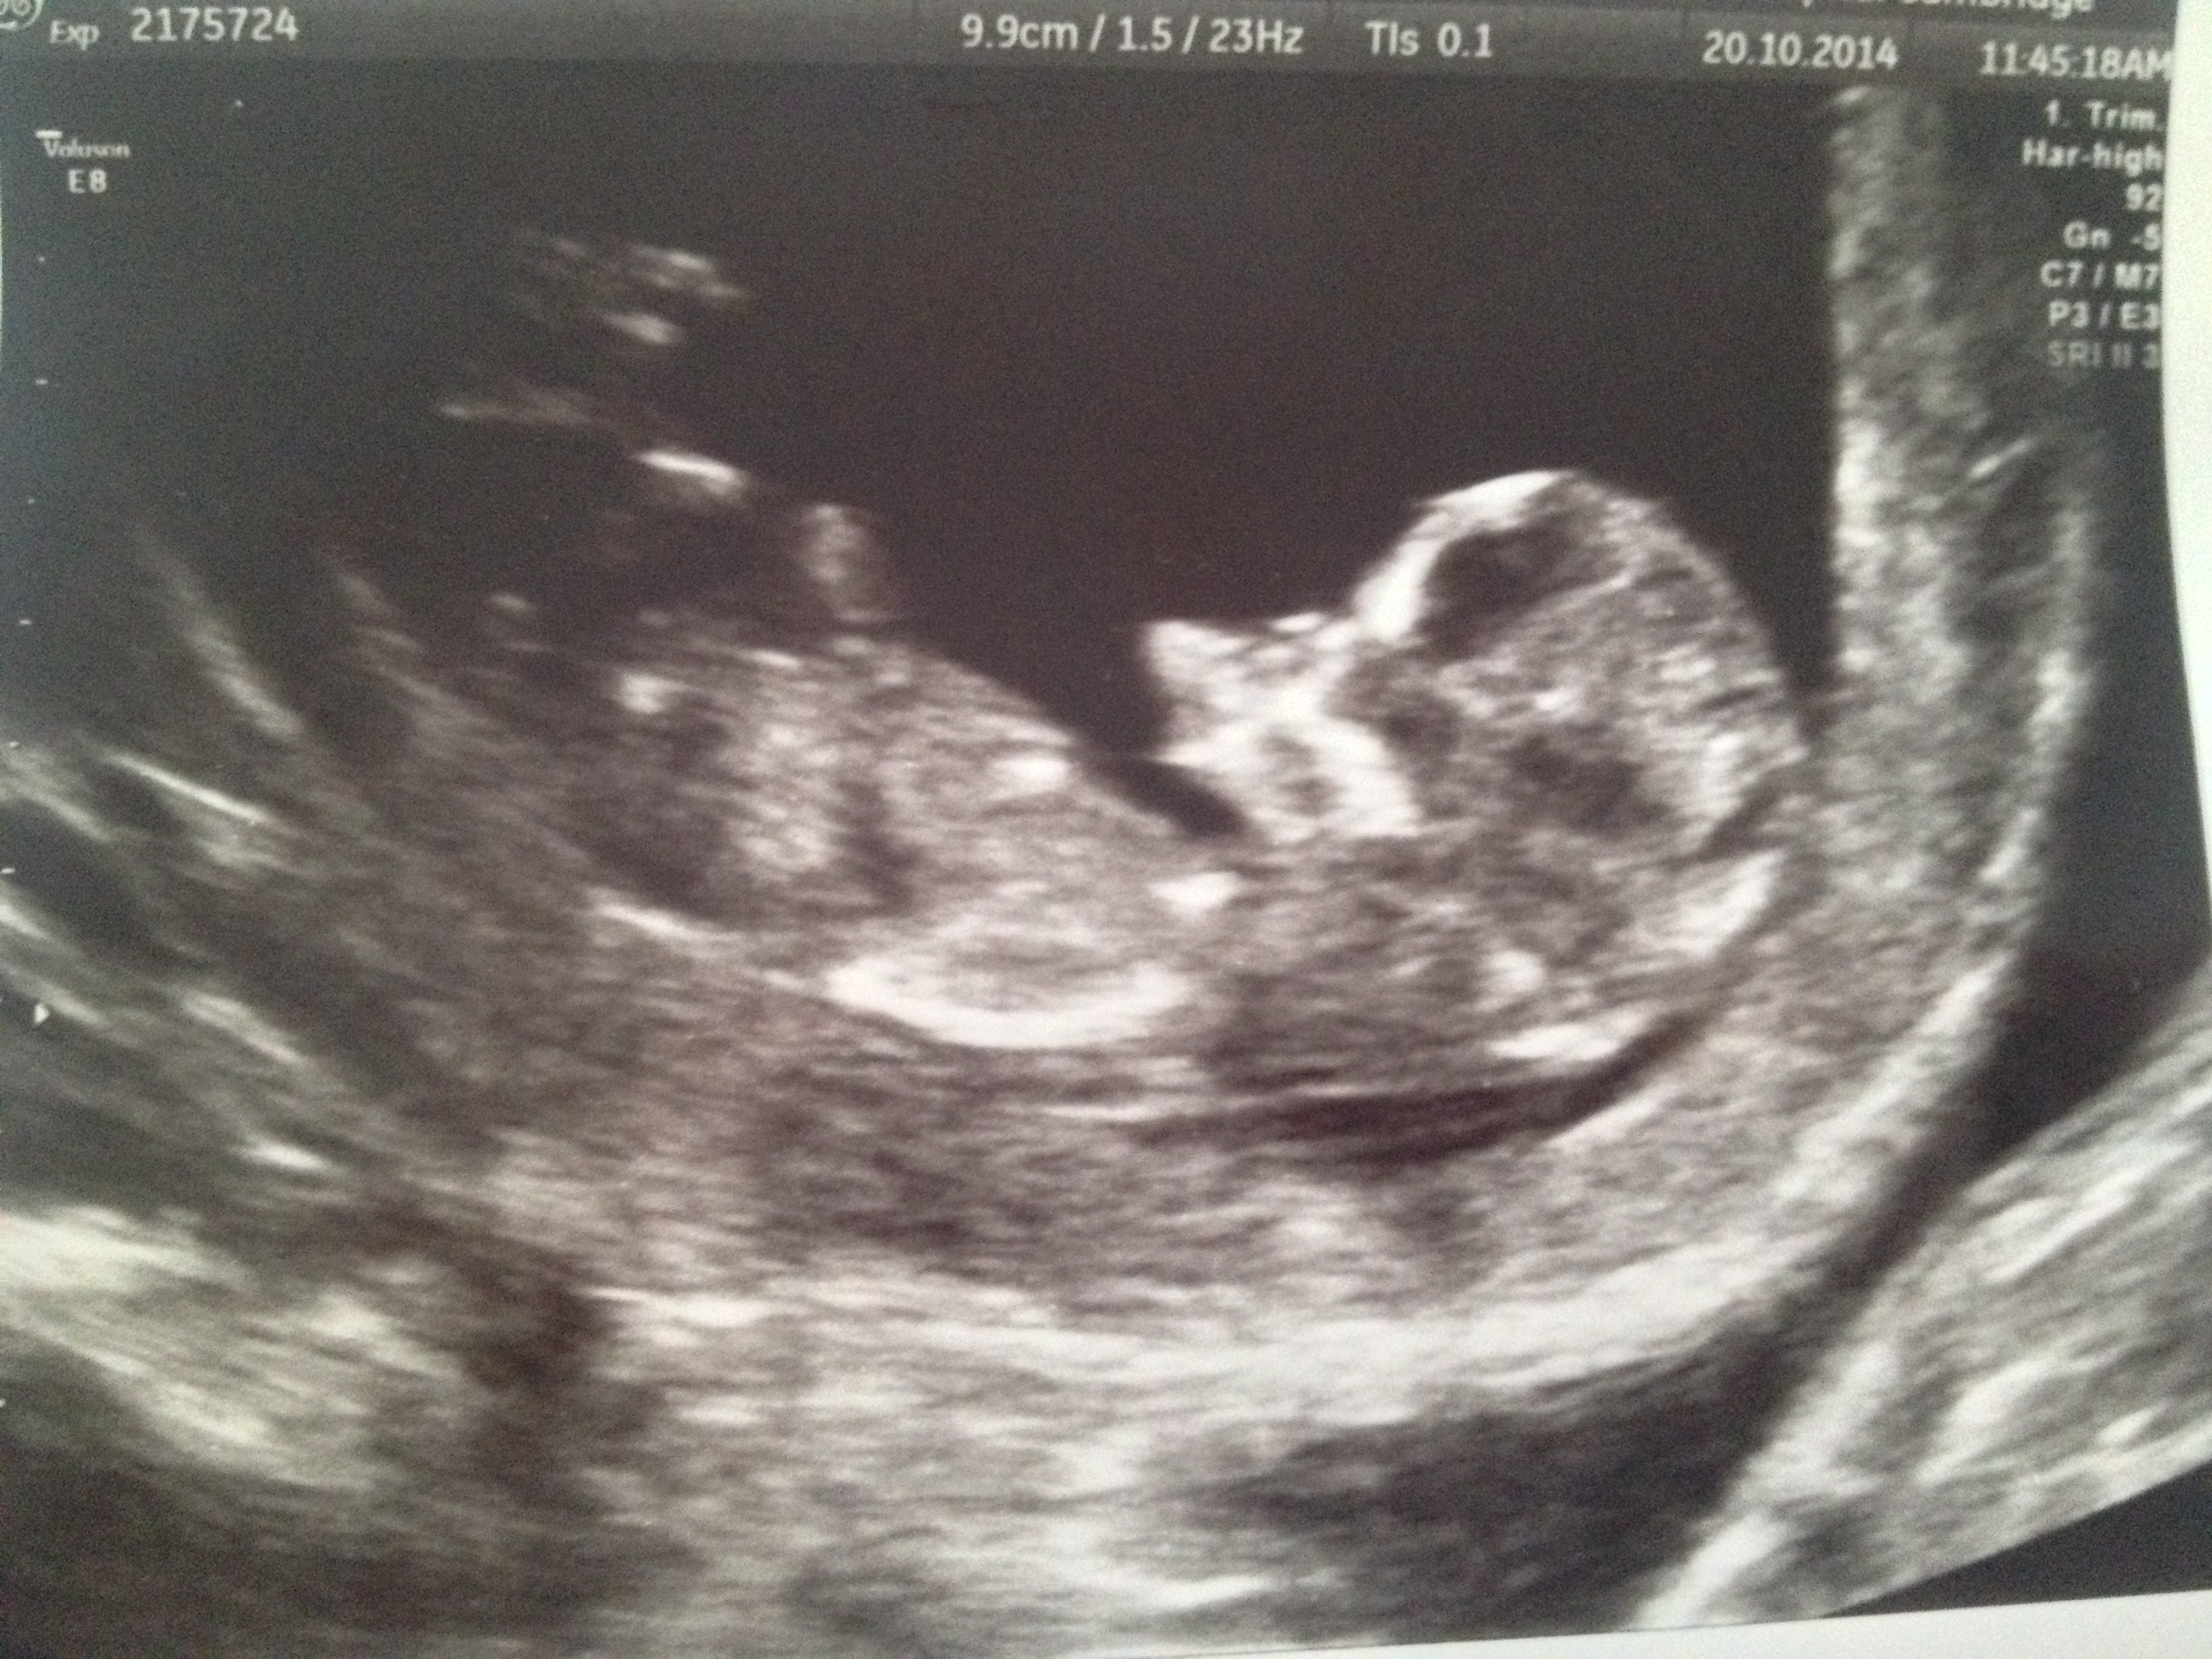

Attachment 22162Attachment 22163 Any guesses?

Thanks to everyone for their guesses so far. Anyone else?